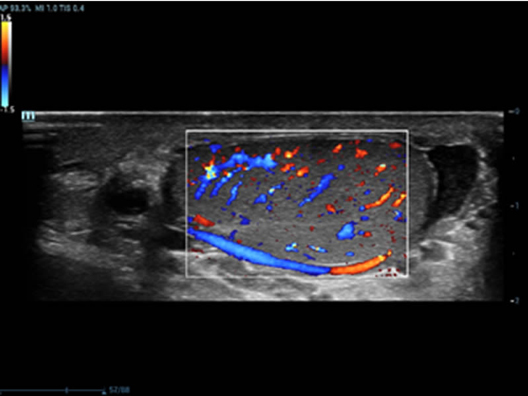

Selain kualitas gambar premium, Resona 7 juga meningkatkan kemampuan penelitian klinis dengan V Flow revolusioner untuk evaluasi hemodinamika vaskular, serta pengambilan penampang tercanggih dari rangkaian data 3D untuk diagnosis CNS pada janin. Kombinasi pengoperasian multisentuh berbasis gerakan yang paling intuitif dengan semua fitur klinis penting membuat Resona 7 menjadi gebrakan baru dalam inovasi ultrasound.